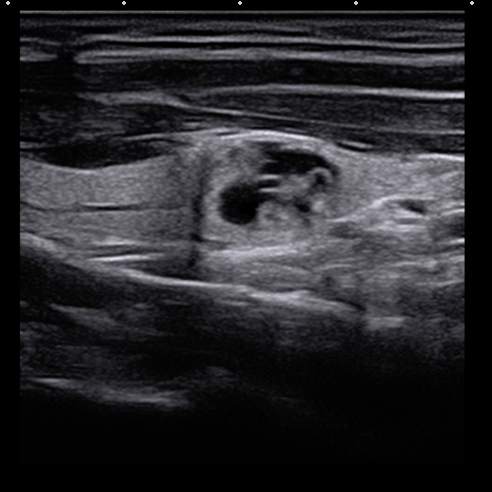

04、看囊实性

依据结节内部成分的不同可以将结节分为:

1. 囊性结节:内部成分为液体;

2. 实性结节:内部成分为固体;

3. 囊实性结节:内部成分既有液体,也有固体。

恶变的几率依次为:实性结节>囊实性结节>单个的囊性结节>多发的囊性结节。

甲状腺囊性,囊实性和实性结节超声图像